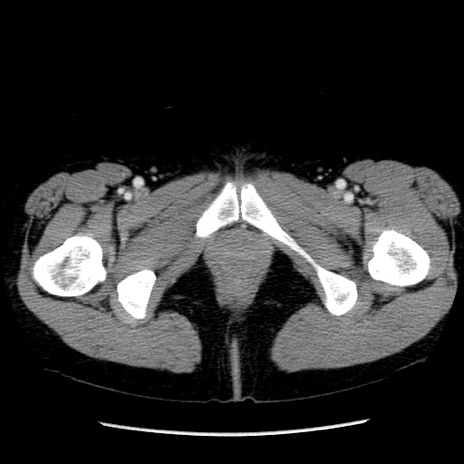

症例6(横断像)

【症例】50歳代女性

【主訴】下腹部痛

【現病歴】本日朝より下痢2回あり。 昼食を食べた後、嘔吐3回、下腹部痛認め、症状軽快せず、当院救急搬送。

最終食事:本日昼(生ものなし)。 昨日の夜、刺身を食ぺたとのこと。周囲に同様の症状の者なし。普段、排便は毎日あるとのこと。

【既往歴】卵巣癌術後(8年前に当院で卵巣摘出)

【身体所見】 意識清明、腹部:平坦、腸蠕動音→、やや硬、下腹部自発痛・圧痛あり、反跳痛あり、筋性防御なし。

【データ】WBC 16000、CRP 0.01